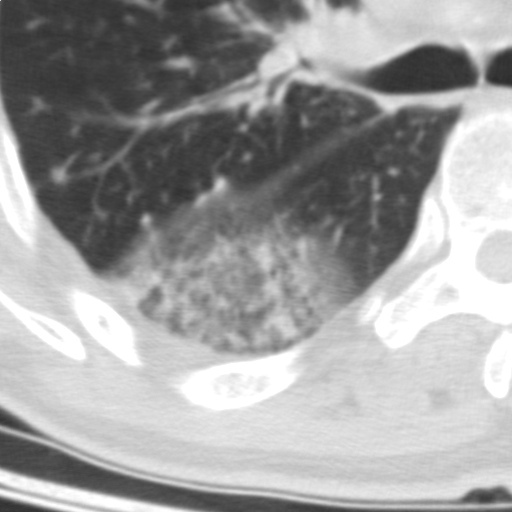

以下是引用随光逐影在2009-5-1 13:53:00的发言:[br]考虑为:1)两肺血行播散型肺结核;2)右肺下叶炎症感染。3)右侧胸膜增厚。